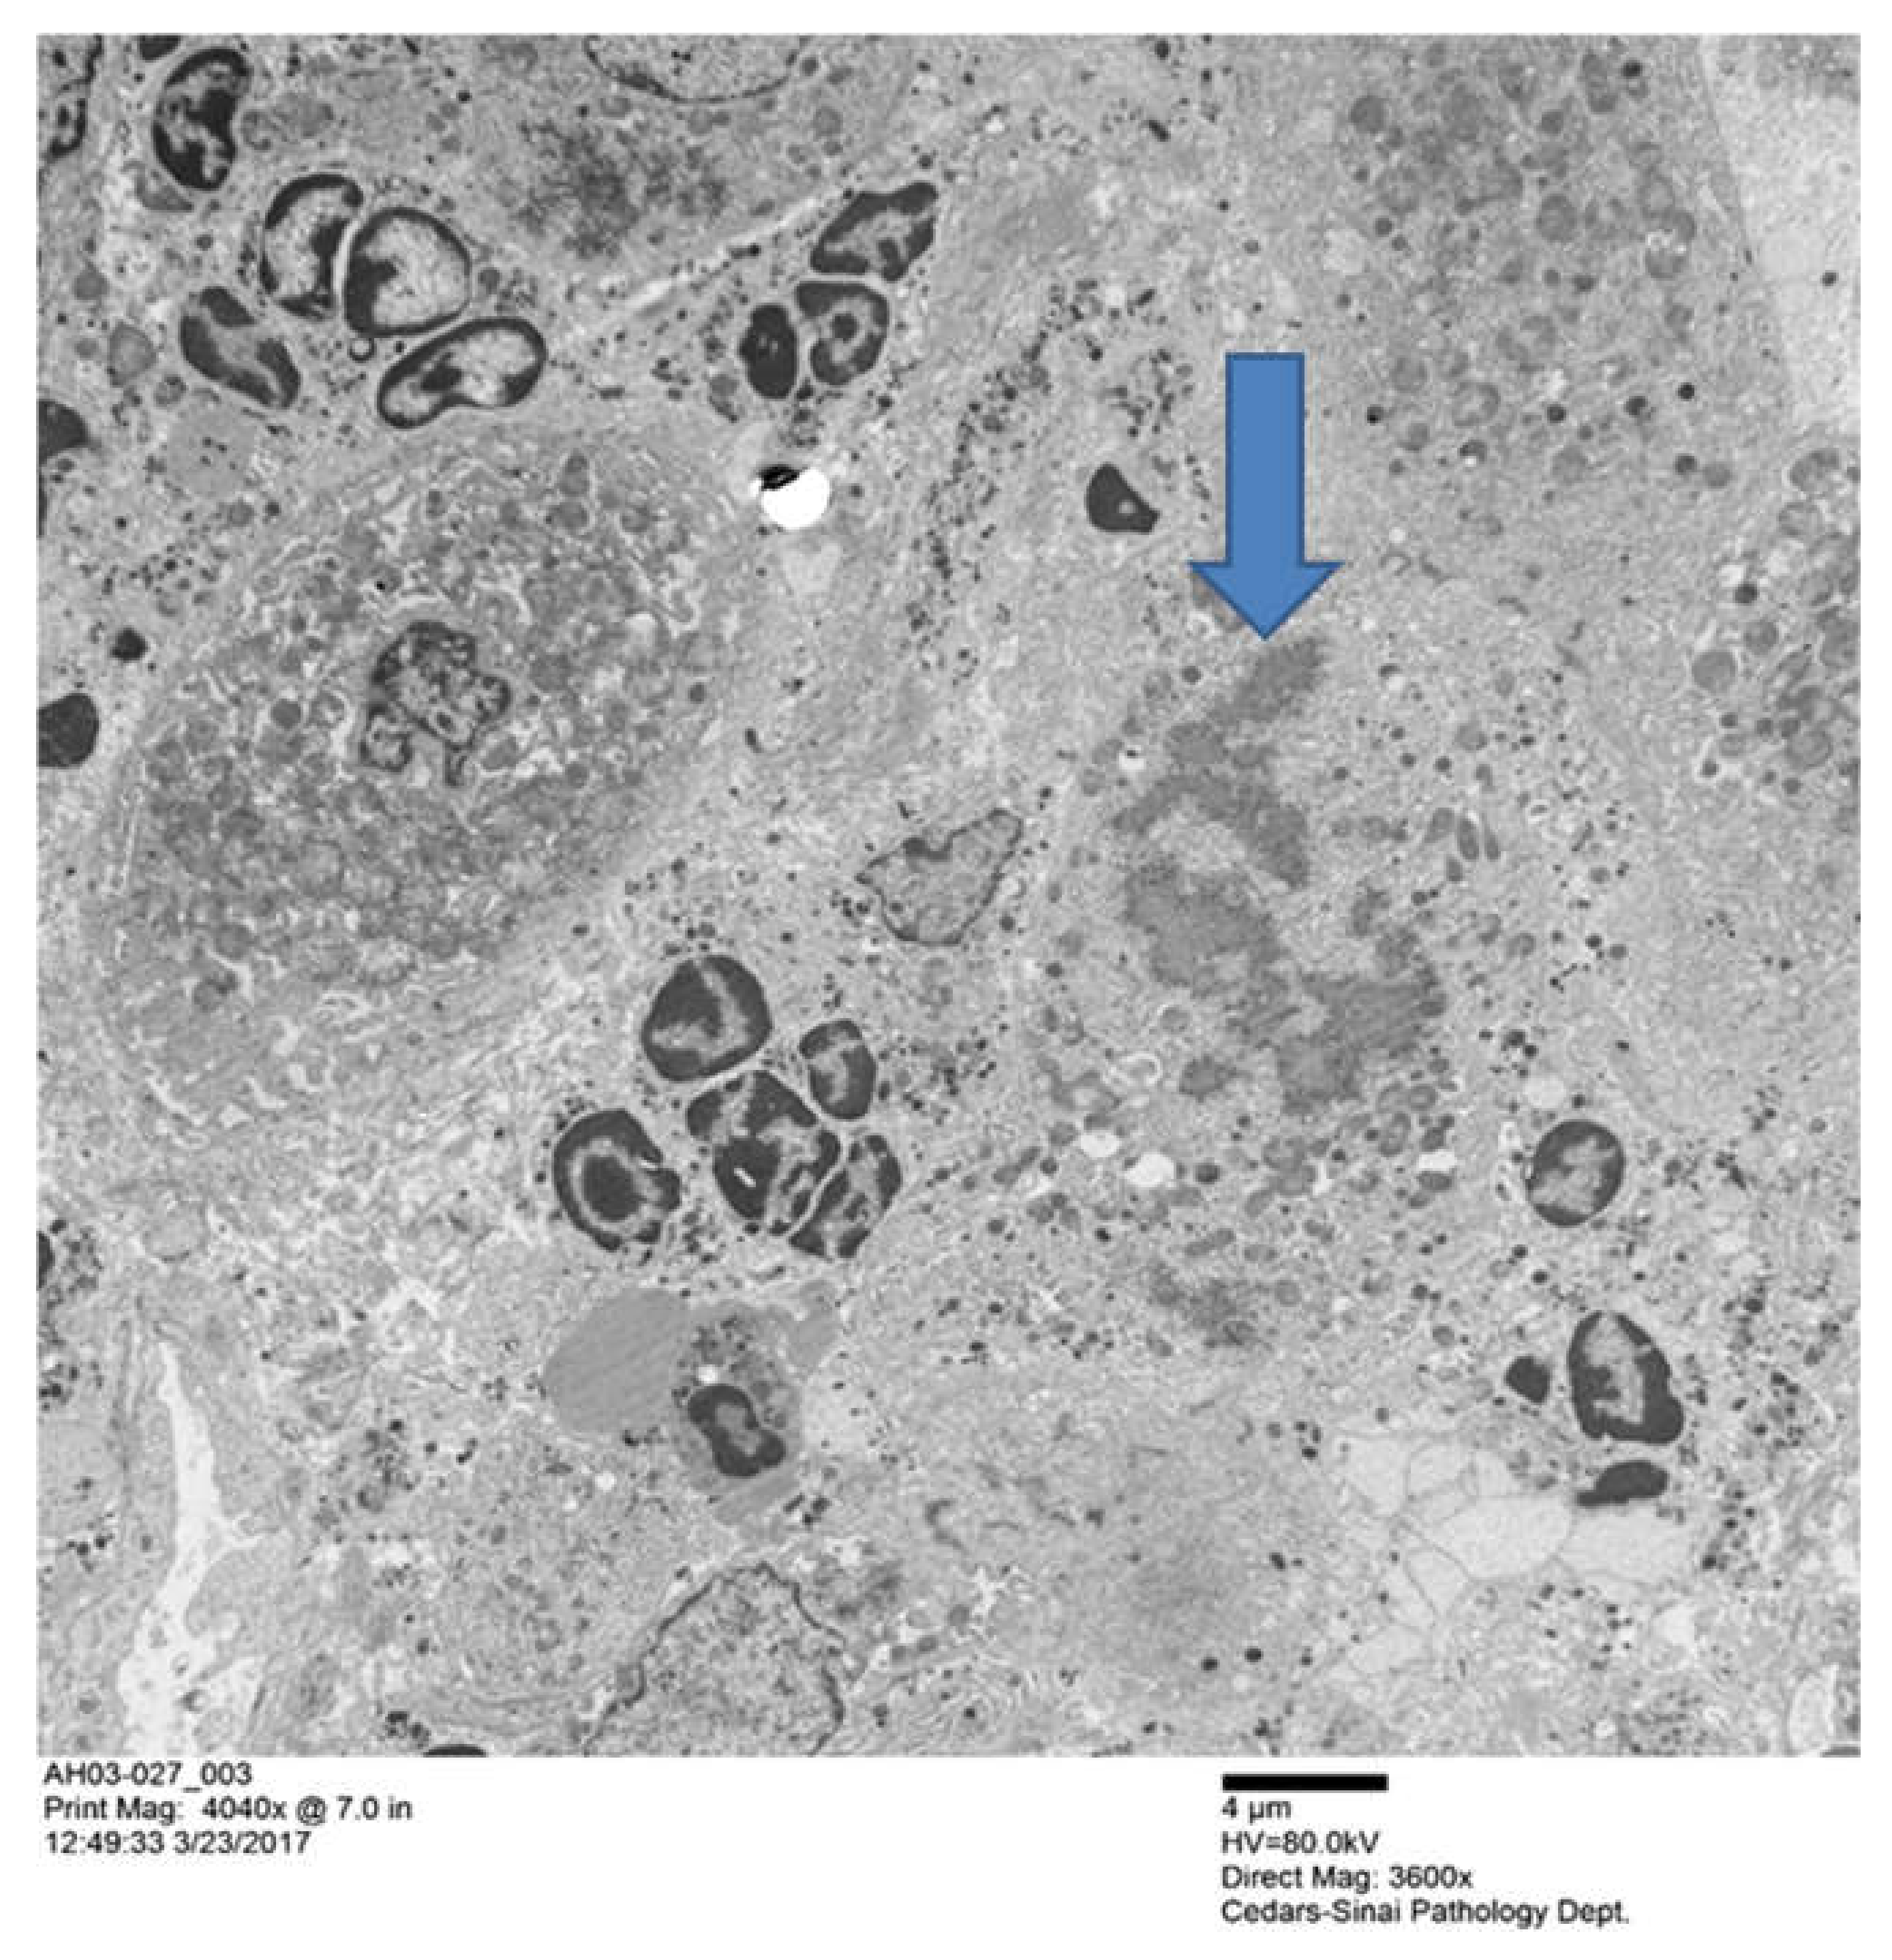

The biopsy slide was stained with an antibody to myeloperoxidase as well as Hematoxylin & Eosin (H&E) staining [39] showing numerous neutrophyils, similar to those seen in Figure 1. This confirms that the GNA15 stained positive for neutrophyils. The myeloperoxidase stain also showed that sinusoids were filled with numerous neutrophyils. Electron microscopy of the liver biopsies showed satellitosis of the granulocytes around and next to the MDB-forming hepatocytes (Figure 2).

Groups of polymorpho neutrophils (PMN)s with condensed chromatin nuclei, clustered around two hepatocytes that had formed MDBs. The arrow pointed the MDB the MDB (× 4040).